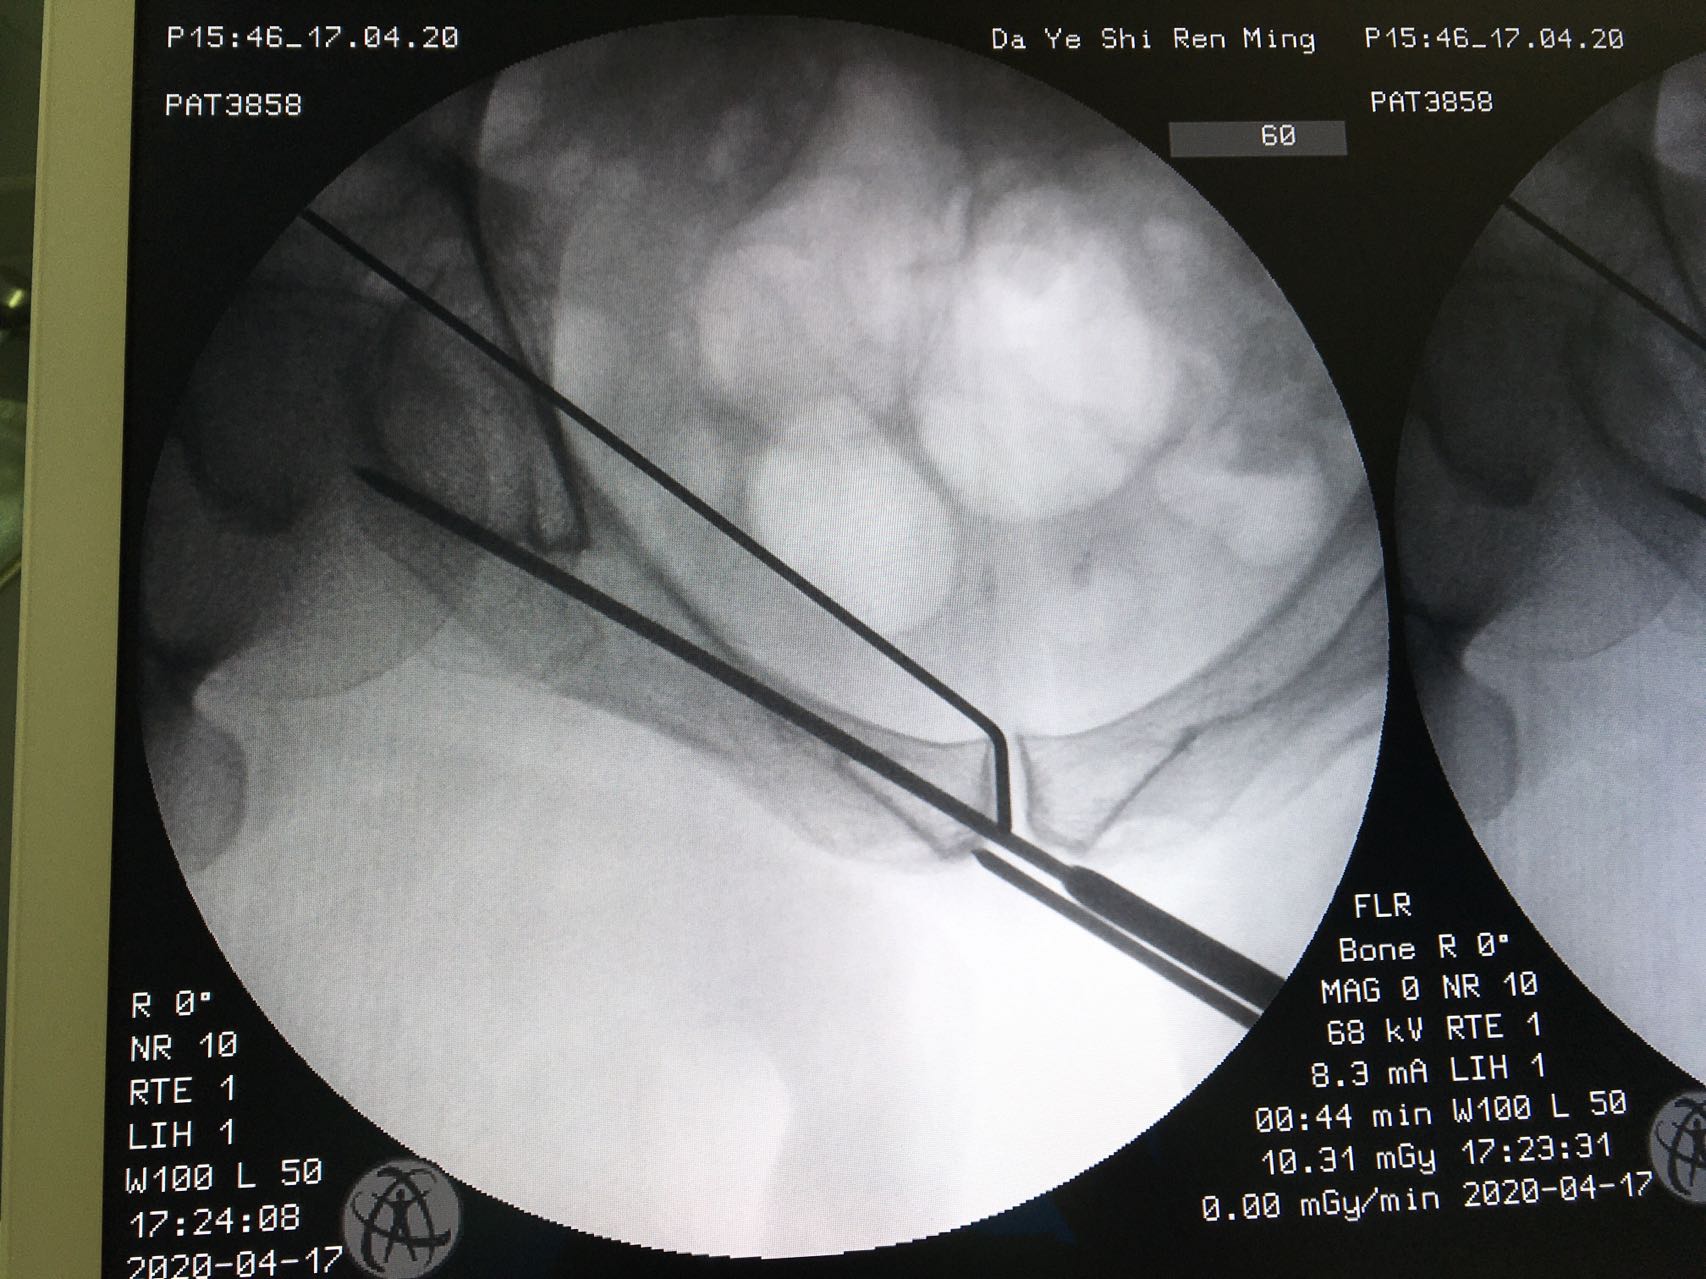

备皮,消毒,摆好透视机器,反复透视,确定最佳的进针点,确定最佳进针方向,一点不能马虎。因为进针的路很窄,旁边也都是重要的人体结构。

骨盆入口位

导针在位

进针点很好